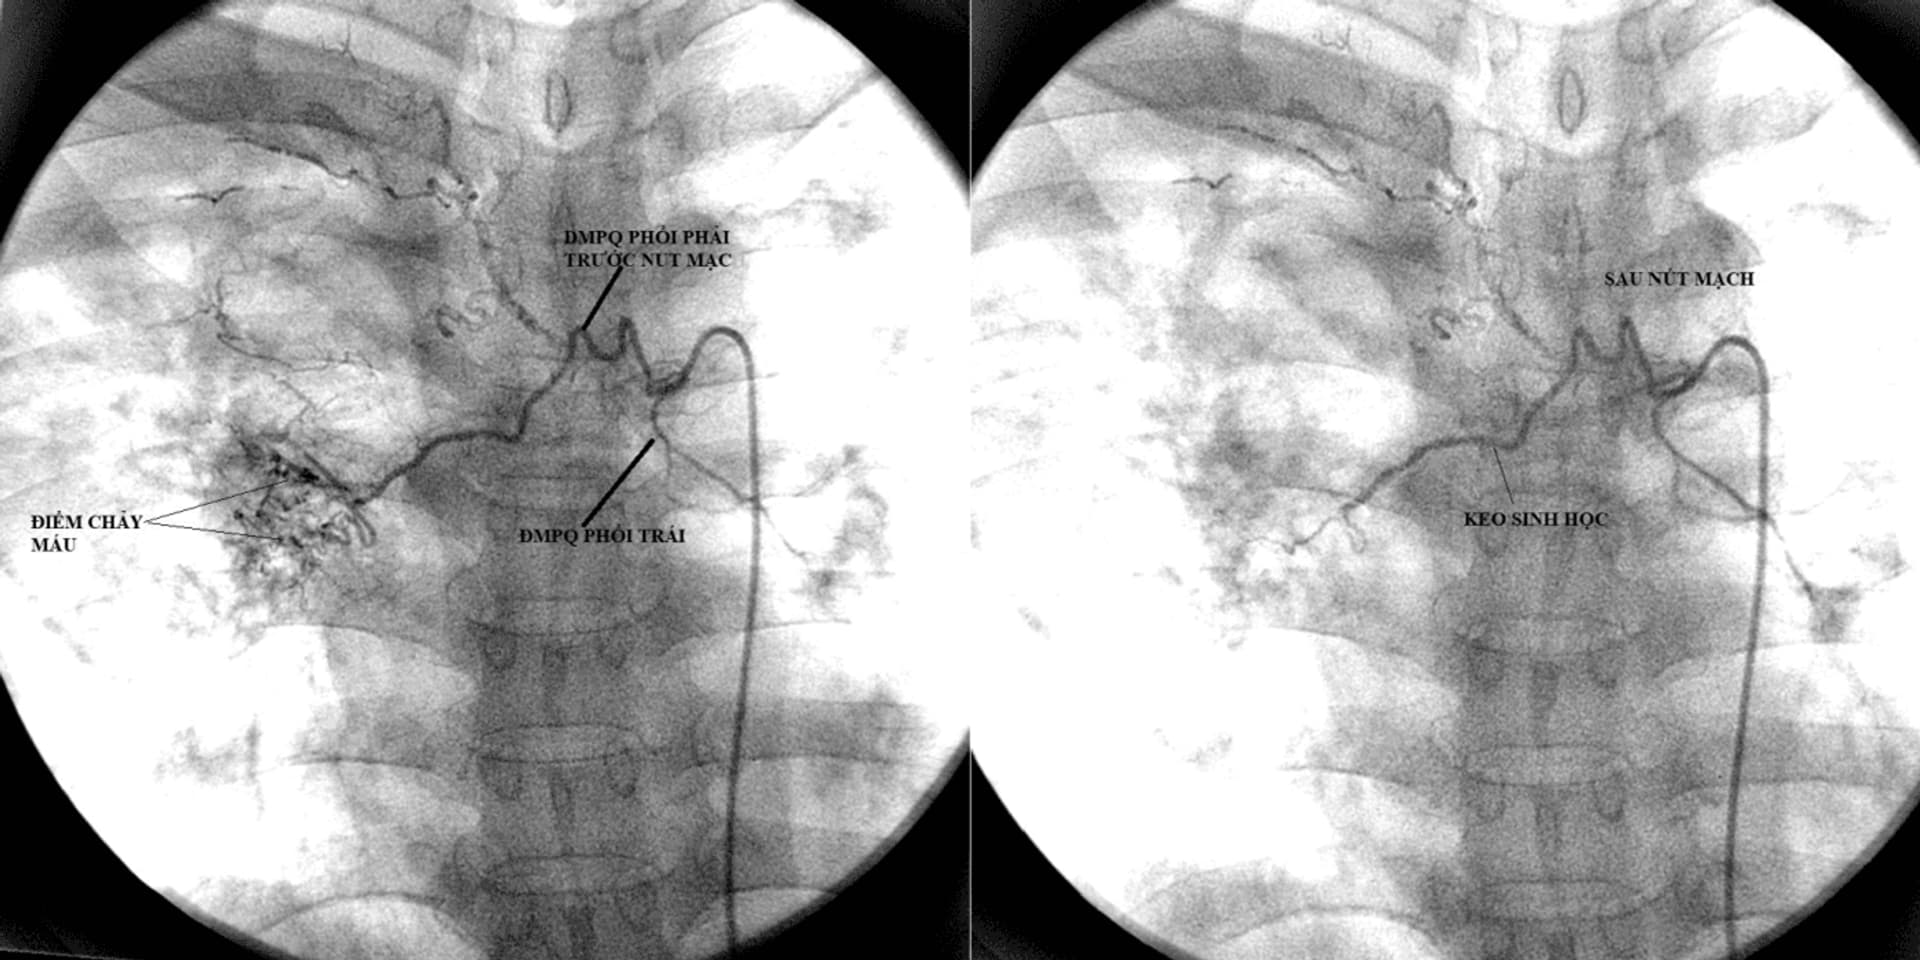

Tại khoa Cấp cứu, các quy trình chẩn đoán và điều trị ho ra máu luôn được cập nhật theo các hướng dẫn quốc tế. Các kỹ thuật hiện đại trong điều trị như nút mạch phế quản, nút mạch phổi, phẫu thuật cầm máu, phẫu thuật cắt tổn thương, cắt thùy phổi… đều sánh ngang tầm khu vực và quốc tế. Ngay sau khi có đầy đủ kết quả xét nghiệm người bệnh sẽ được hội chẩn với các chuyên gia đầu ngành về hồi sức cấp cứu, chẩn đoán hình ảnh, can thiệp mạch, chuyên gia phẫu thuật lồng ngực, gây mê hồi sức, giải phẫu bệnh, vi sinh… để đưa ra phương án điều trị can thiệp hiệu quả nhất. Sự phối hợp nhịp nhàng, nhanh chóng giữa các khoa lâm sàng, cận lâm sàng cũng là một trong những yếu tố quan trọng để cứu sống người bệnh. Không chỉ được tiếp cận kỹ thuật chẩn đoán, điều trị hiện đại nhất, tại khoa Cấp cứu, bệnh nhân còn được tiếp cận dịch vụ chăm sóc toàn diện: Tư vấn giáo dục sức khỏe, hướng dẫn chế độ nghỉ ngơi, dinh dưỡng, động viên tinh thần người bệnh…

Kỹ thuật nút và chụp mạch phế quản cầm máu